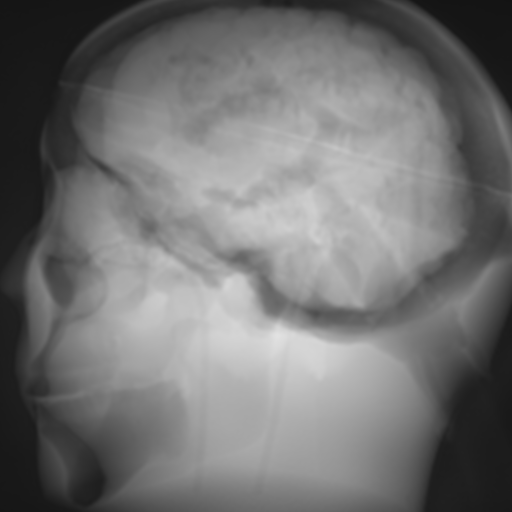

(f) Input: MR proj.

Refer to caption

(g) Output: U-net 1subscript1\ell_{1}-loss.

(h) Output: ResNet 1subscript1\ell_{1}-loss.

(i) Output: CRN 1subscript1\ell_{1}-loss.

(j) Reference: X-ray proj.

Figure 2: Results of the projection synthesis. Top row: Results generated with the perceptual-loss function. Bottom row: Results generated with the 1subscript1\ell_{1}-loss function.

The quantitative and qualitative results of the proposed experiments are presented in Table I and Figure 2. By examining these it can be observed that the differences in the calculated MSE of all network architectures and incorporated loss functions are only small. The best results in terms of pixel-wise deviation could be achieved with the ResNet architecture combined with the 1subscript1\ell_{1}-loss function. This network achieves a deviation from the reference of only 0.058, i.e., 2.4 percent. Also the results of the U-net and CRN networks are still good with deviations of 2.6 and 2.9 percent. Similarly small variation can be observed in the structured similarity measure. The ResNet and CRN exhibit approximately equal quality with SSIM measures of 0.938 and 0.920 for the 1subscript1\ell_{1}-loss and 0.924 and 0.931 for the perceptual-loss, respectively. The results generated with the U-net are slightly worse. The highest peak signal-to-noise ratio is achieved by the ResNet (1subscript1\ell_{1}-loss), followed by the U-net (1subscript1\ell_{1}-loss) and CRN (p-loss). It is noteworthy that the ResNet and U-net both achieve the highest results in all error metrics using the 1subscript1\ell_{1}-loss while the opposite is the case for the CRN which works best with the perceptual-loss function.

Overall, the perceptual-loss achieves competitive and in some cases even better results than the 1subscript1\ell_{1}-loss when comparing the pixel-wise error metrics. For example, the cascaded refinement network’s MSE is 0.013 smaller for the perceptual- than for the 1subscript1\ell_{1}-loss. This might be suspicious at first sight, considering that the 1subscript1\ell_{1}-loss purely optimizes for this pixel-wise error in the training process while the perceptual-loss compares the raw feature activations of the evaluation network. Contrarily, this behavior cannot be observed for the U-net and ResNet. The results produced with the 1subscript1\ell_{1}-loss achieve higher values for all error measures for these networks. An explanation for this obervation is that the intensity values of the input image still cause an impact on the respective layers output in the evaluation network when computing the perceptual-loss. Consequently, these differences also transition to the computed loss value for all feature layers. Even though the perceptual-loss incorporates the raw intensity values, it is not guaranteed that the scaling of these is conserved in this process. By this, the relative changes can be similar, whereas the absolute range of values changes and, correspondingly, also the pixel-wise error metrics.

Another observation is that the perceptual-loss is able to conserve high-frequency details in the image. The fine line in the projection images that forms a circle around the cranium is visible in the input (Figures 2a & 2f), as well as in the label images (Figures 2e & 2j), and also in the images generated with the perceptual-loss function (Figures 2b2c, and 2d). In contrast, all generators ”loose” this line when the 11\ell 1-loss is applied (Figures 2g2h, and 2i). This effect is also qualitatively observable in other parts of the images. Despite achieving equal or better results regarding the error metrics, the generally less sharp look of the results generated with the 11\ell 1-loss function is apparent. This behavior is in accordance with previous observations that concluded that an perceptual-loss leads to sharper images than a comparable 11\ell 1-loss [19]. Considering the common applications of X-ray Fluoroscopy, e.g., interventional guidance for stents and similar devices, high spatial resolution is a key requirement. Utilizing a loss function that is able to preserve high-frequency details in the images is desirable to this end. The perceptual-loss appears to be suited for this task as presented in our evaluation.